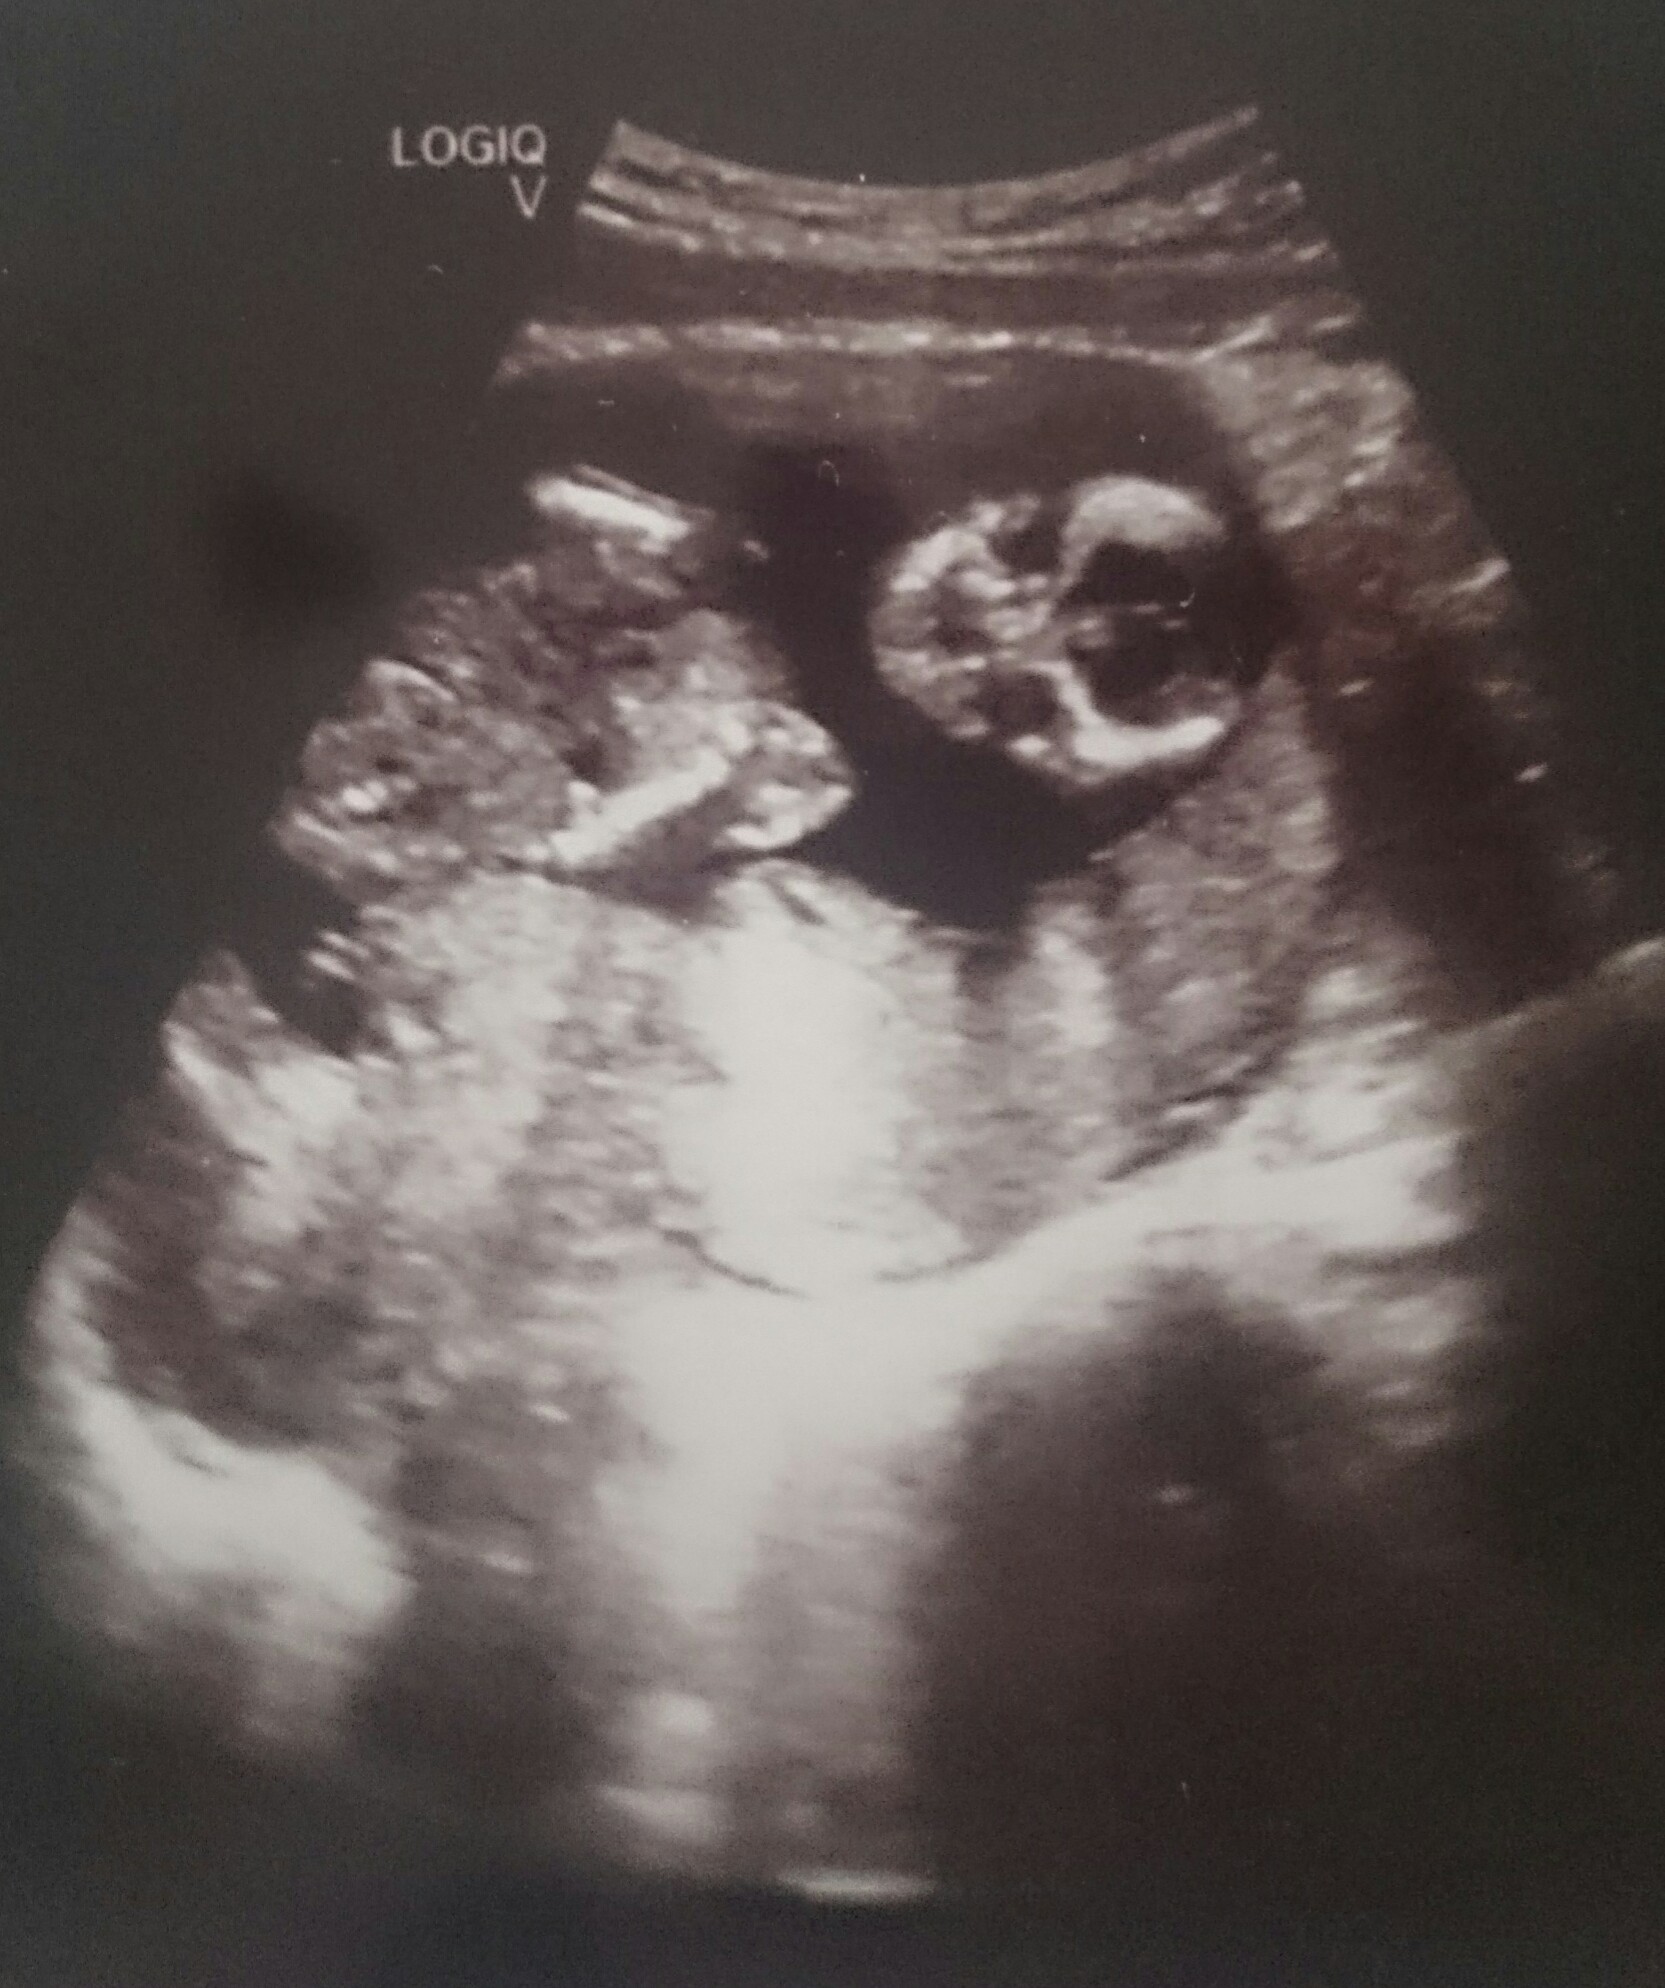

W 14/15tc zdarza sie ze labia jest nabrzmiala. Może to mylic ze cos odstaje. Talze joshi antiope macie szanse na pannę jeszcze.

No ja Anecie pisałam ze ta co odstaje na 3d u niej na zdjęciu to może być siusiak ale niekoniecznie. Wyszlo ze jednak sie schowalo